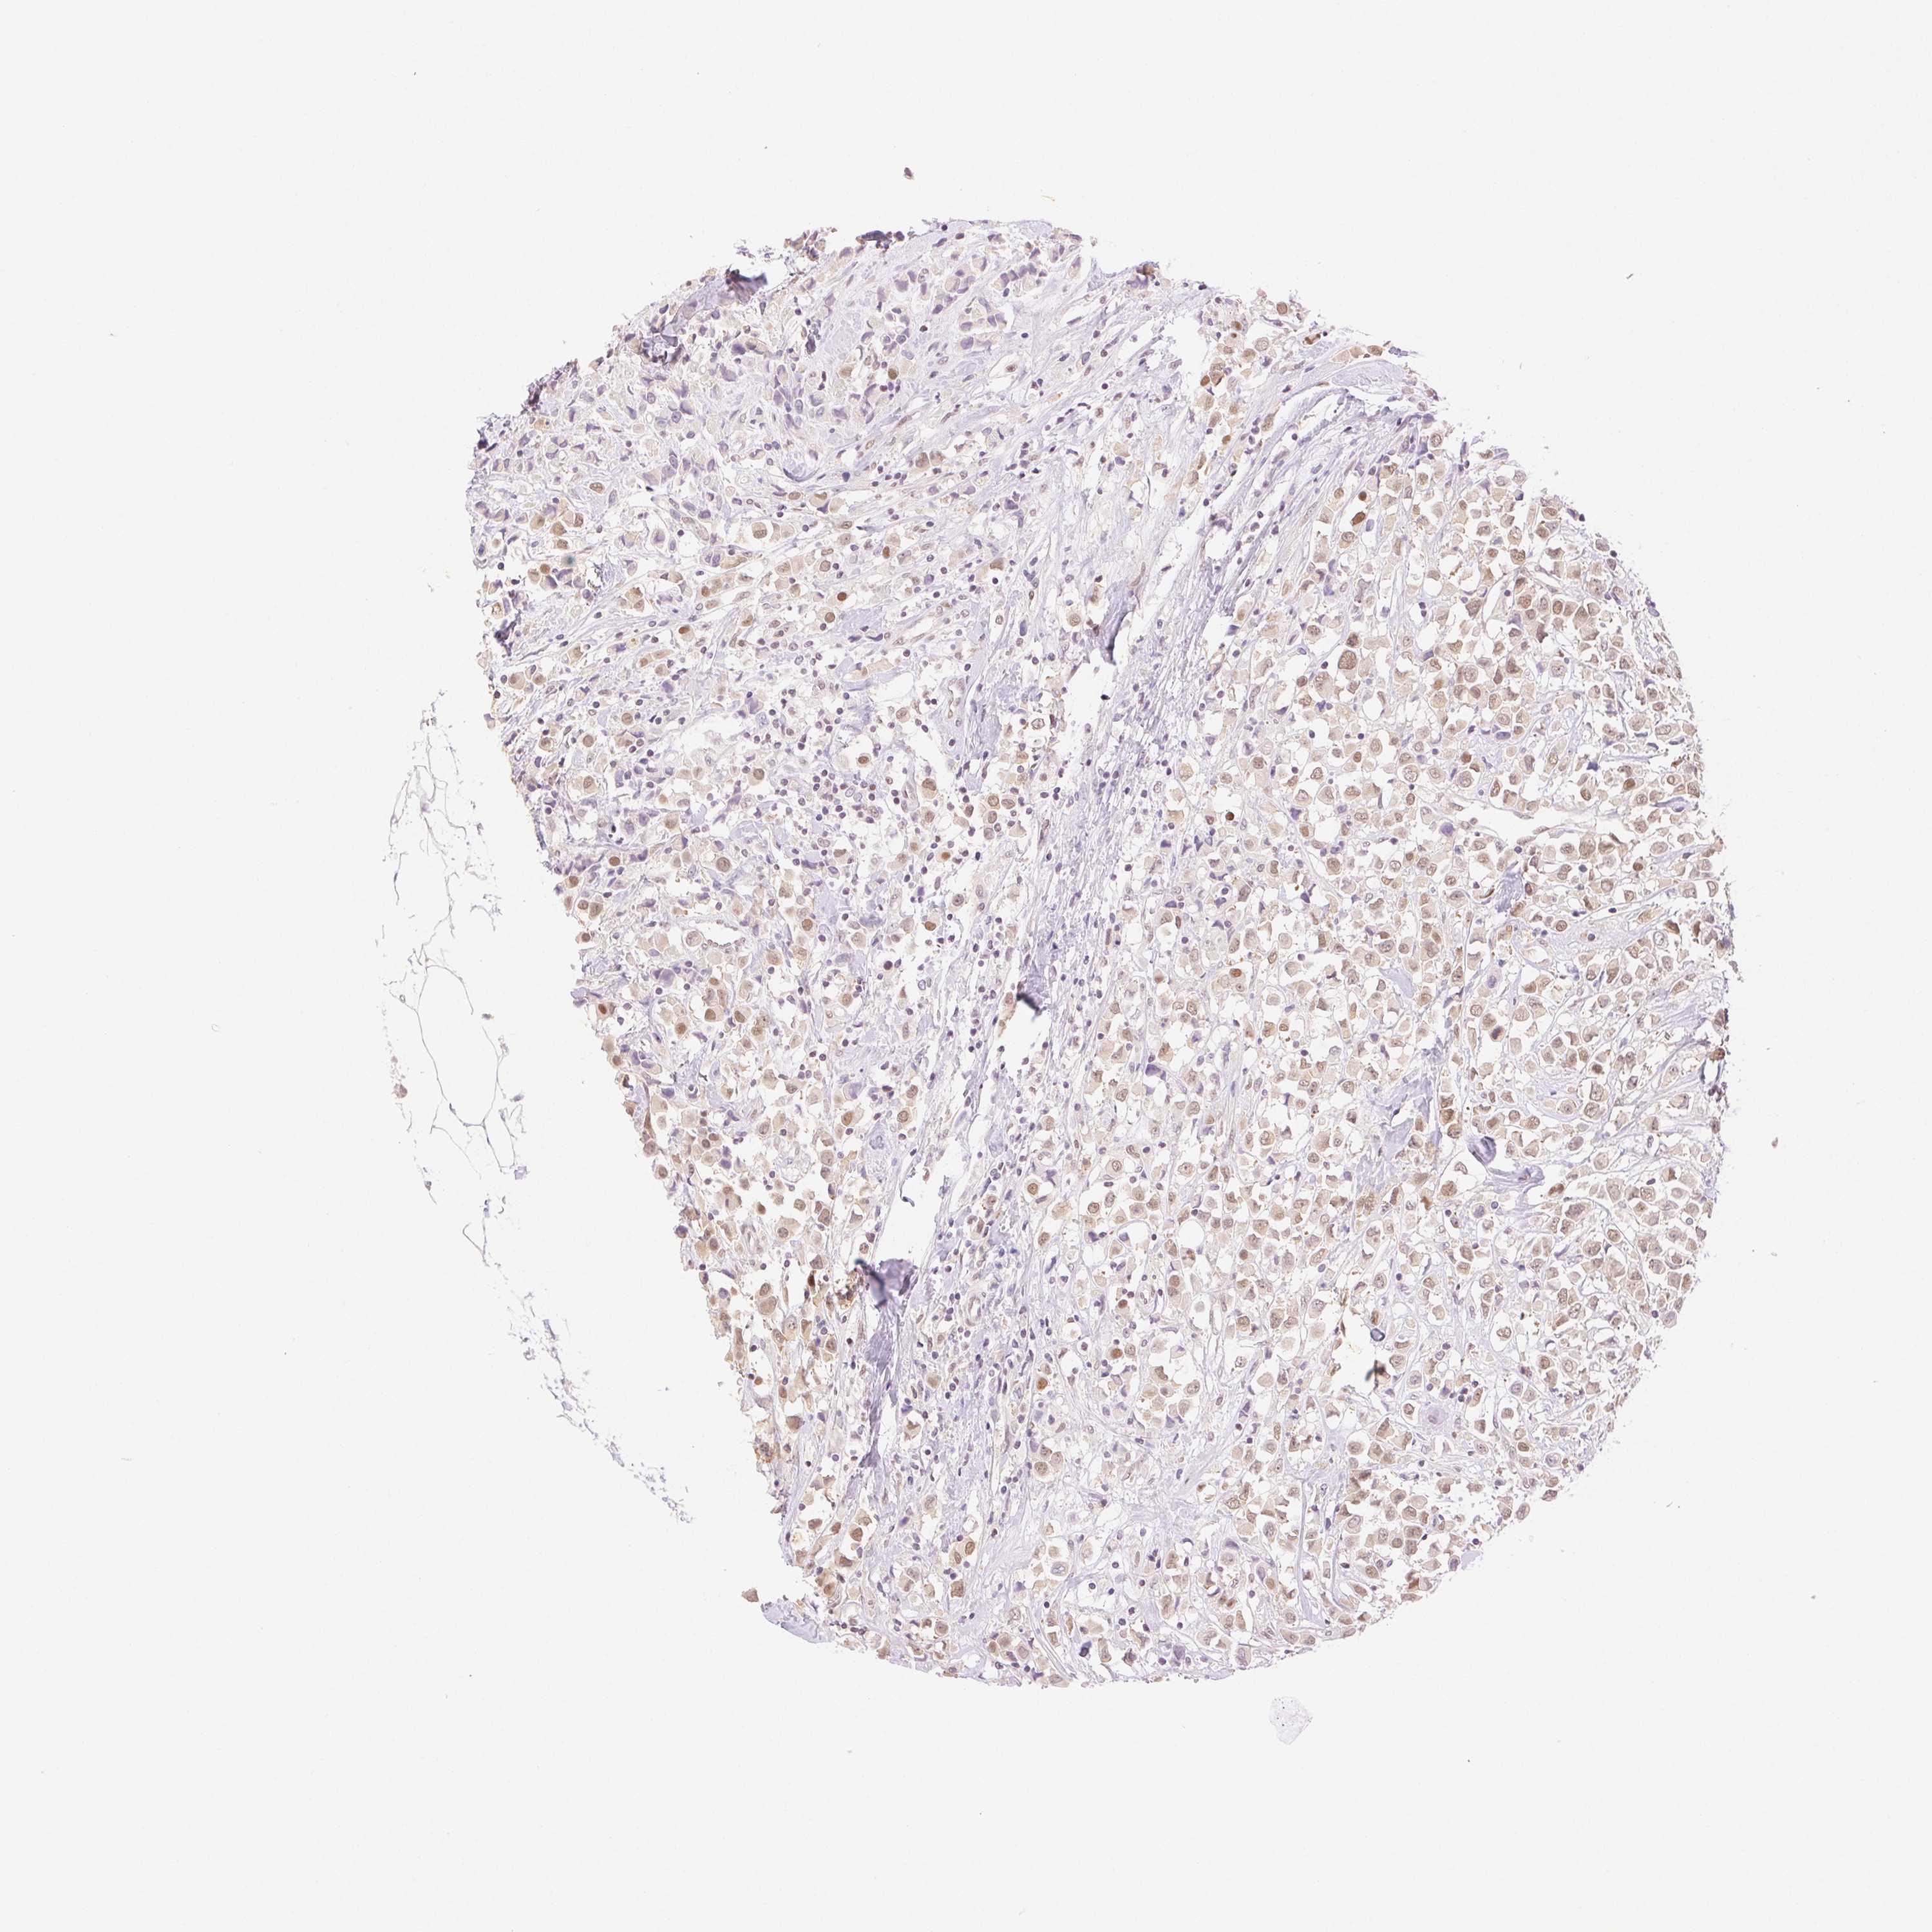

CANCER BREAST CANCER Show tissue menu

BRCA TCGA BRCA VALIDATION PROTEIN EXPRESSION

ANTIBODIES

AND

VALIDATION